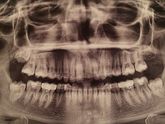

11 февраля 2017 20:59 Вы удаляли зуб мудрости после снятия брекетов,и как сильно на этом настаивал ваш врач?У меня даже нет зубов мудрости,а ортодонт вовсю кричит,что надо его удалить или иначе будет все в прежнем состоянии?